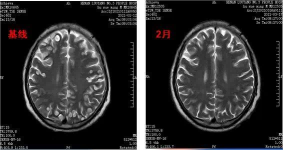

四、治疗前后对比图

脑部肿瘤治疗前后对比